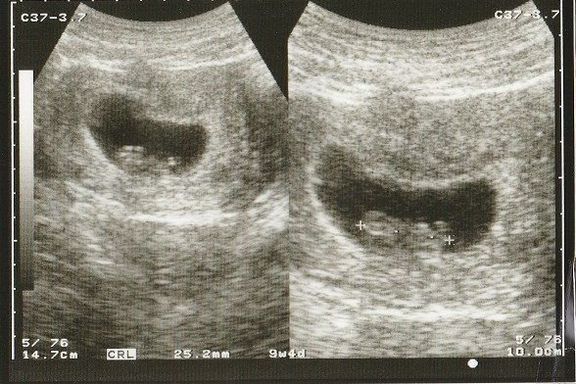

命の始まりは神秘的!2D・3D・4Dのエコー写真で見る「私と赤ちゃんの実録260日」 -

"おなかの中はどうなっていくの? エコー写真で振り返る、高齢ママのはじめての妊娠生活" -